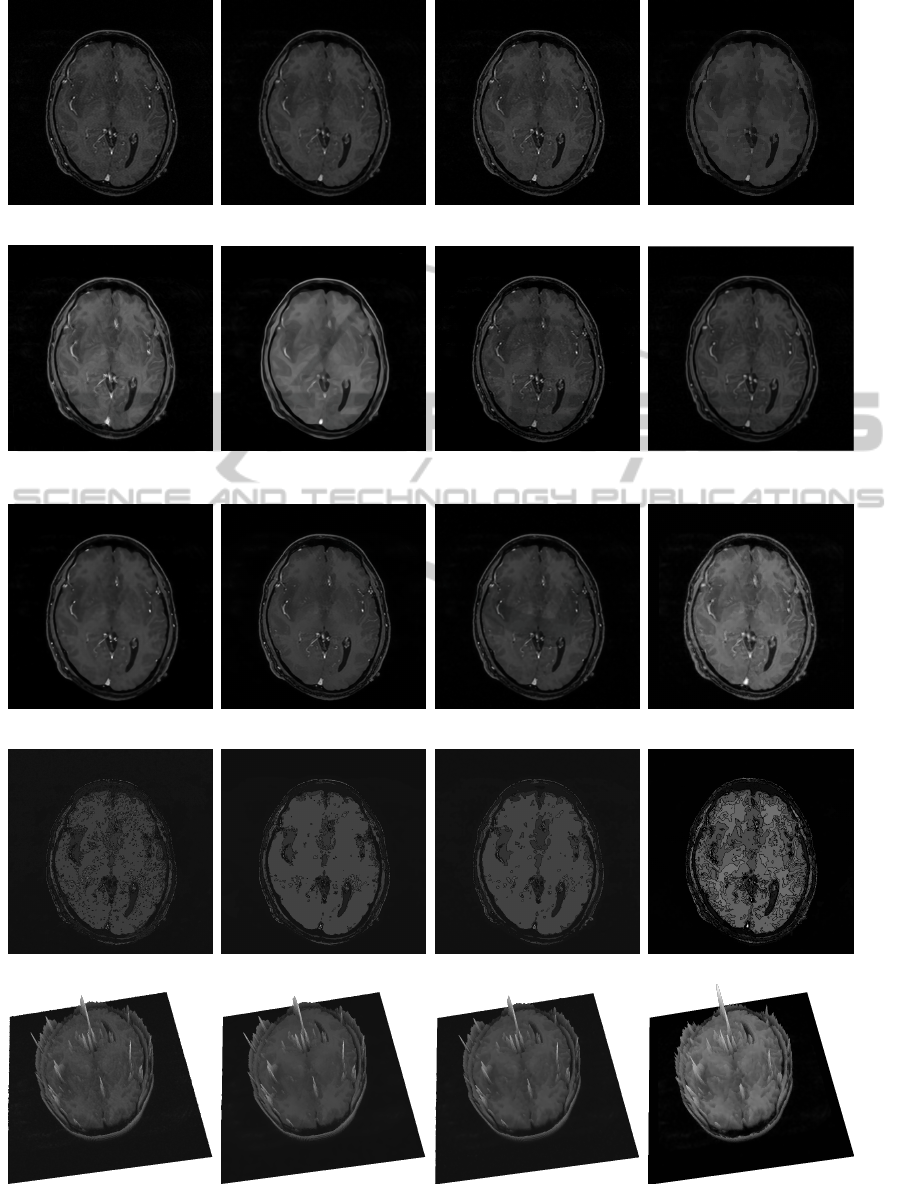

In the image presented in Fig.2(a), the aim is to

smooth the noise present in the images while preserv-

ing both the white and the grey matters. We used

our detector with µ = 5, λ = 1.5 and ∆θ = 5

◦

for re-

gions classification. The threshold for the edge/region

classifier s

th

is equal to 0.002. Parameters used in

anisotropic edge detector in order to compute (θ

1

,θ

2

)

are µ = 5, λ = 1 and ∆θ = 2

. The results of our

anisotropic diffusion are presented in the Fig. 2(l).

Note that the limit between the grey and the white

matter is perfectly visible, Fig. 2(t) illustrates the

sharpness of this edge.

In order to show the efficiency of our method for

noise removal and edge of grey/white matter contours

enhancement, we show the image surface of our re-

sults. The 3D elevation of our result allows to see

that grey/white matter edges are well preserved and

sharped. Figs. 2 (m), (n), (o) and (p) show the

isophotes (curves of the image surface of constant in-

tensity) according to 15 levels. It is visible that our

approach preserves also small objects which could be

a tumor or a default inside the brain.